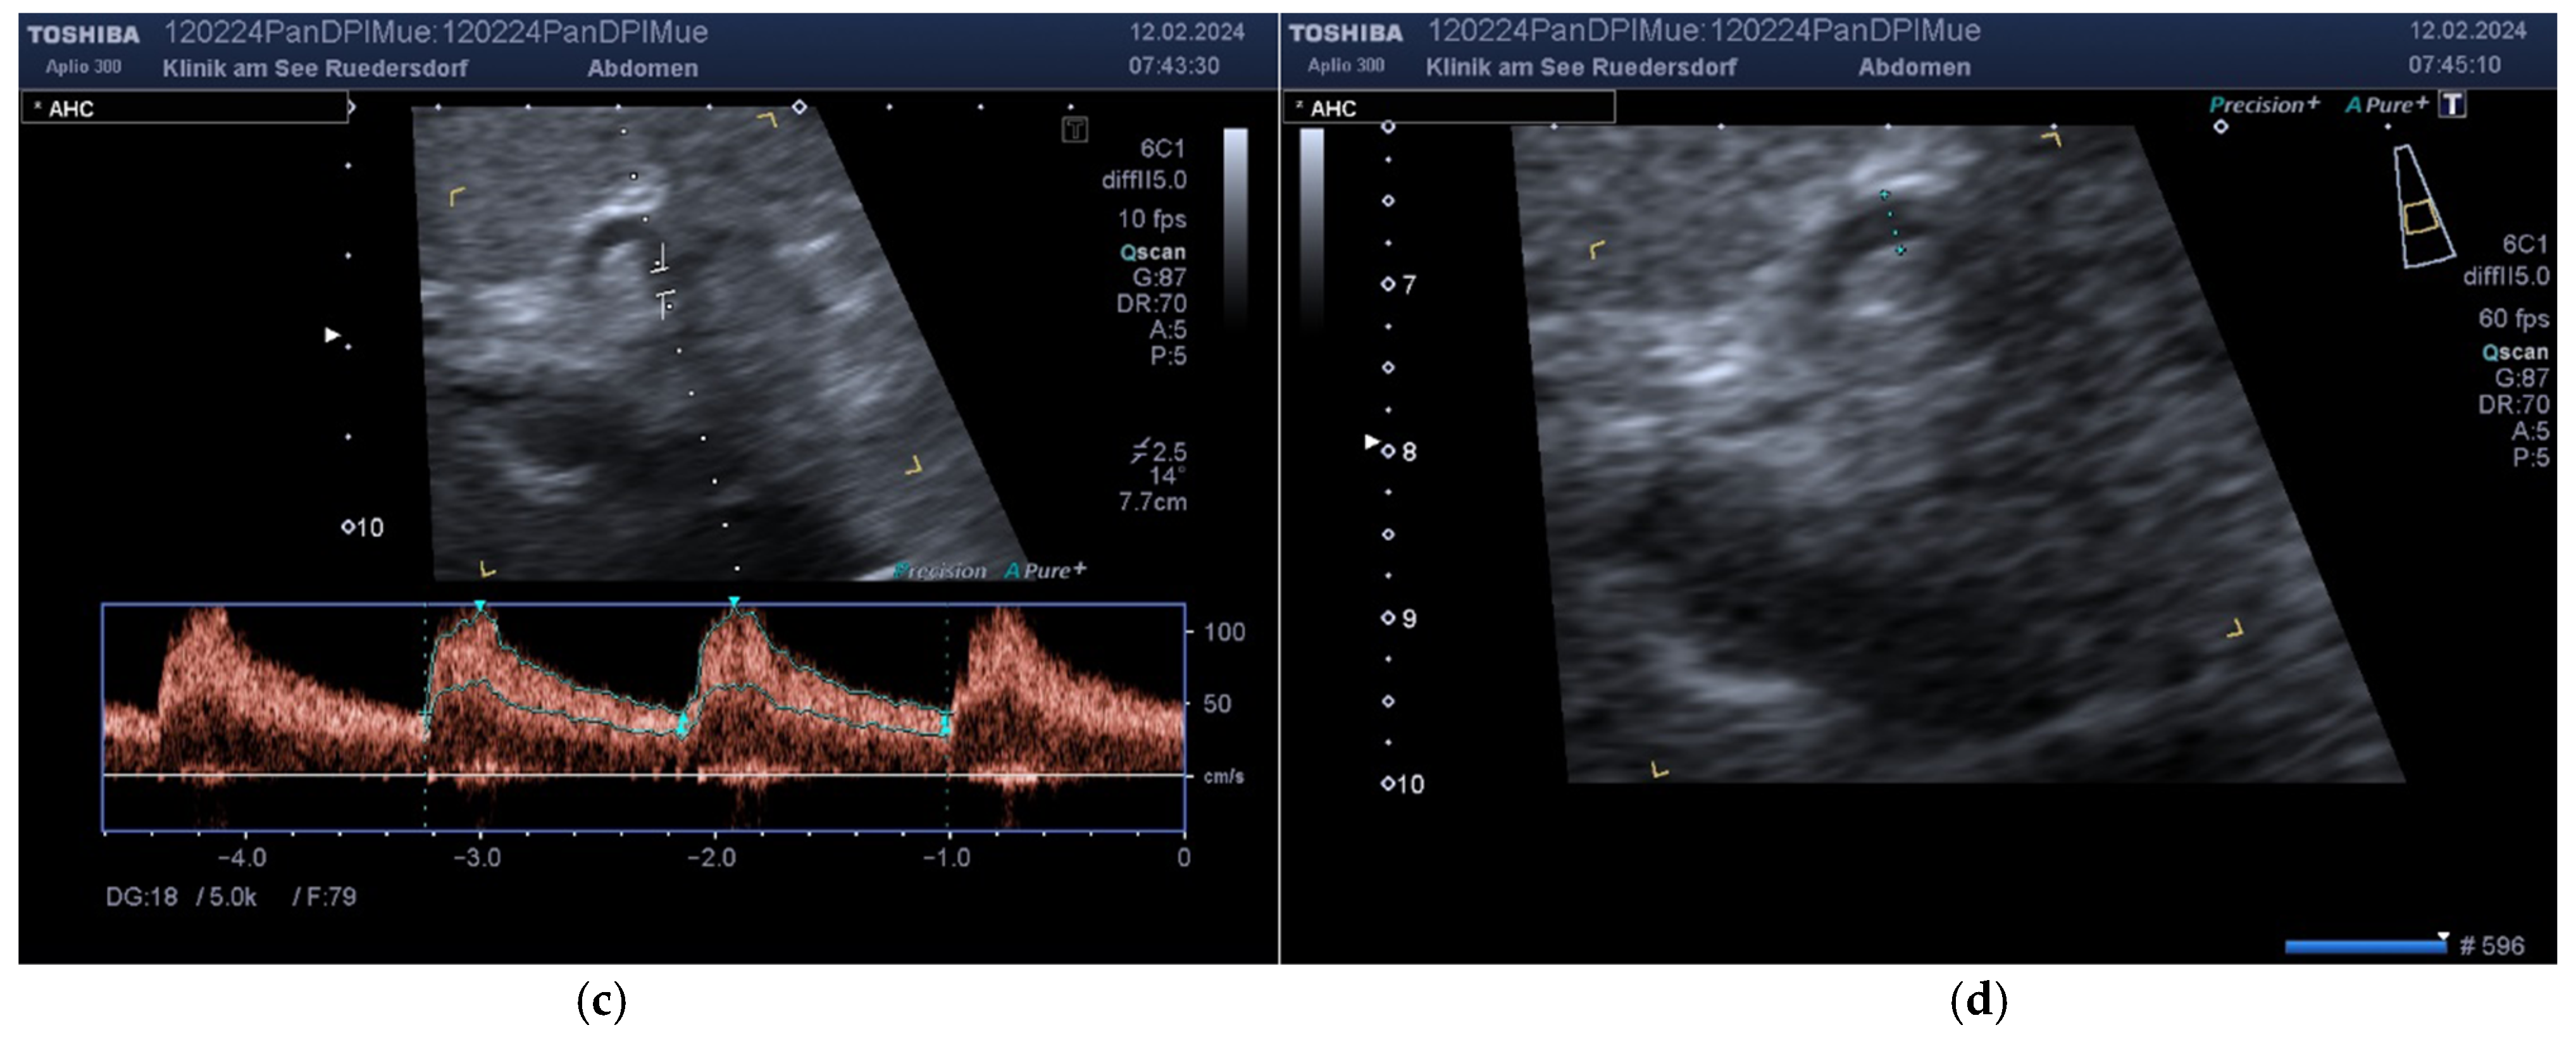

2.3.1. Determination of Vessel Diameter

2.3.2. Location of the Probe, Insonation Angle, and Doppler Window

3.2. Measured Values and Calculated Blood Flow